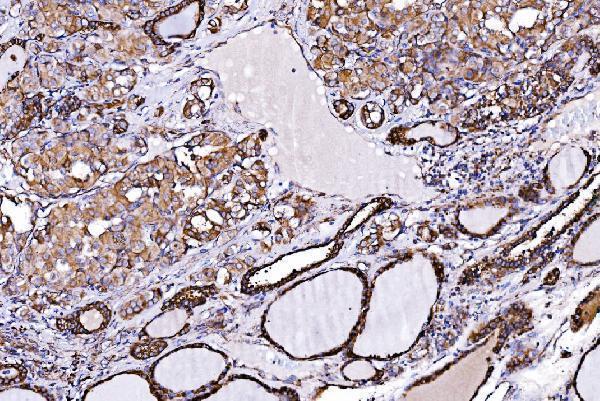

IHC analysis of ORP150/HYOU1 using anti-ORP150/HYOU1 antibody (A04934-2).

ORP150/HYOU1 was detected in a paraffin-embedded section of human hyroid papillary carcinoma tissue. Heat mediated antigen retrieval was performed in EDTA buffer (pH 8.0, epitope retrieval solution). The tissue section was blocked with 10% goat serum. The tissue section was then incubated with 2 μg/ml rabbit anti-ORP150/HYOU1 Antibody (A04934-2) overnight at 4°C. Biotinylated goat anti-rabbit IgG was used as secondary antibody and incubated for 30 minutes at 37°C. The tissue section was developed using Strepavidin-Biotin-Complex (SABC) (Catalog # SA1022) with DAB as the chromogen.